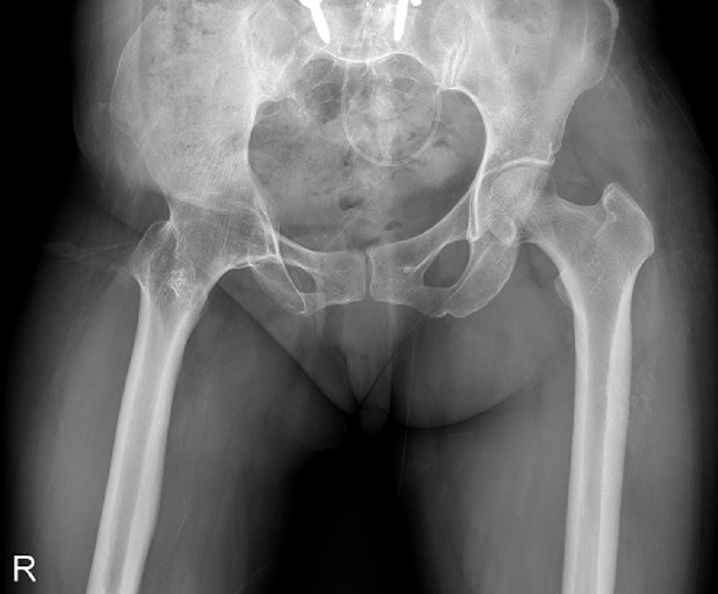

Fig. 4.

Prefracture radiograph of an 8-year-old female patient who presented with a proximal one-third fracture of the left femur (bilateral lower-extremity standing anteroposterior view).

Case 2: osteogenesis imperfecta

An 8-year-old female patient visited our emergency room complaining of pain in the left thigh that began on the day of her visit. She slipped and directly injured her thigh upon falling to the left. Initial examination revealed normal laboratory findings, including serum calcium levels of 9.0 mg/dL and inorganic phosphorus levels of 4.7 mg/dL. Radiographic evaluations, including anteroposterior and lateral views of the left femur, demonstrated a transverse irregular fracture line in the proximal one-third area of the left femur, accompanied by lateral cortex hypertrophy. Importantly, the possibility of malignancy or infection as contributing factors to the fracture was considered low. Two years prior, the patient had visited the pediatric department of our hospital due to concerns about her height, which was below that of her peers. Following genetic testing, she was diagnosed with osteogenesis imperfecta and has since been monitored by both the pediatrics and orthopedics departments. At that time, lateral bowing of both femurs was observed in both lower extremities during standing anteroposterior evaluations (Figs. 4, 5). She had previously undergone epiphysiodesis on both femurs due to genu valgum. After diagnosis, the patient underwent open reduction and internal fixation using an ender nail. Follow-up evaluations indicated successful bone union at the fracture site.